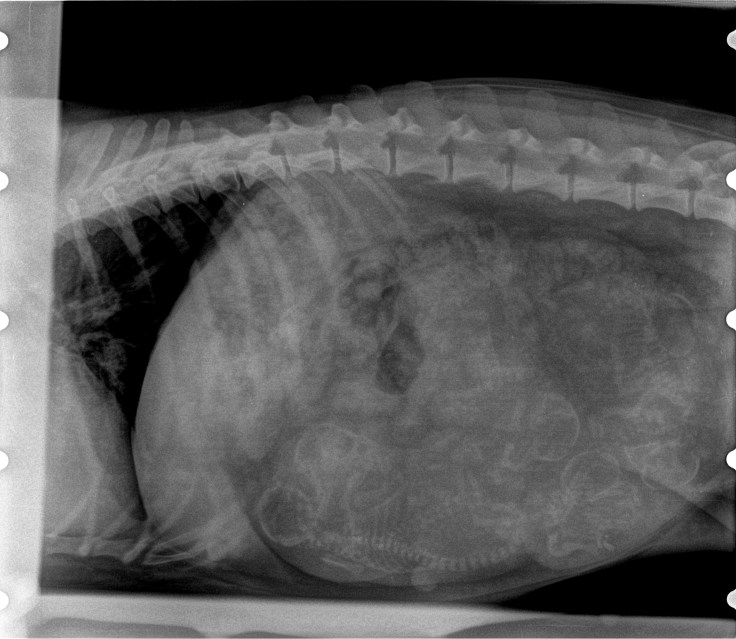

Dracht Dit delen: Delen op X (Opent in een nieuw venster) X Share op Facebook (Opent in een nieuw venster) Facebook Vind-ik-leuk Aan het laden...